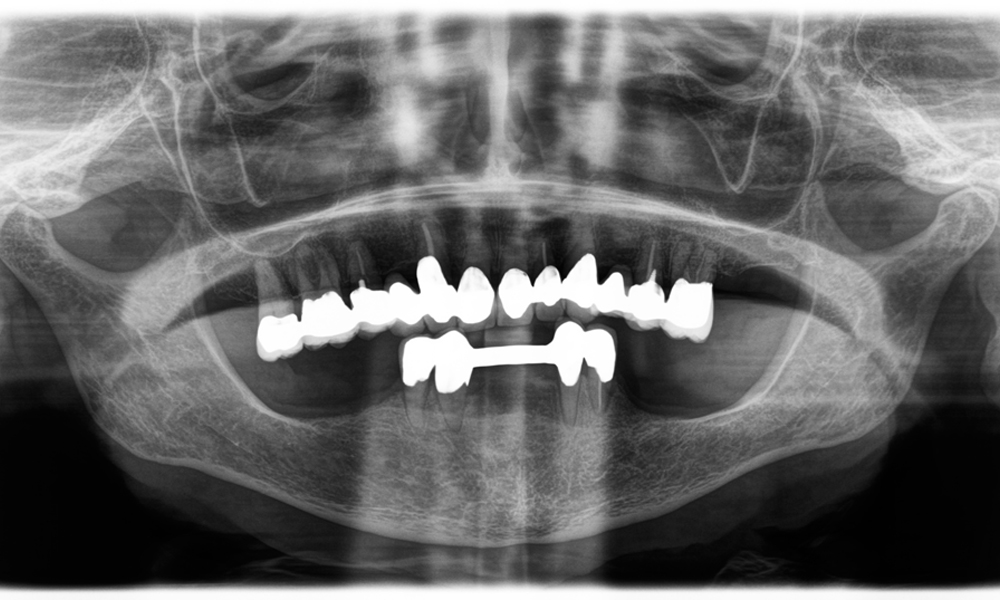

A jaw x-ray from an 81-year-old patient, in front of a black background.

Figure 1: Aesthetic rehabilitation of PFM crowns: Complete removal and replacement of 40-year-old PFM crowns to improve aesthetics in an 81-year-old patient.

Dr Wolfgang Tautschnig, a dentist with extensive experience from Salzburg, has applied and assessed the Synea Power Edition over several months in a range of clinical scenarios, particularly in the removal of zirconia crowns and the processing of base metal alloys. In one specific case, an 81-year-old patient presented seeking aesthetic improvement of her 40-year-old PFM (porcelain-fused-to-metal) crowns. The existing restorations no longer met her expectations in terms of appearance.

The challenge was to remove twelve splinted crowns made of a base metal alloy without damaging the underlying abutment teeth. The handpiece was used to precisely section the ceramic layers and divide the metal framework using a carbide bur, enabling minimally traumatic crown removal. Within just 30 minutes, the old restorations were removed, allowing for the preparation of a new prosthesis, comprising full-contour zirconia in the posterior region and veneered crowns anteriorly. The result was a complete restoration that delivered both functional and aesthetic success (see Fig. 1).